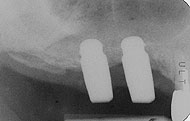

術後の骨結合度の判定

![]() ▲骨植の嵌合度や骨癒着度の判定には歯科用ピンセットの頭で、打診音を聞くのがよい |